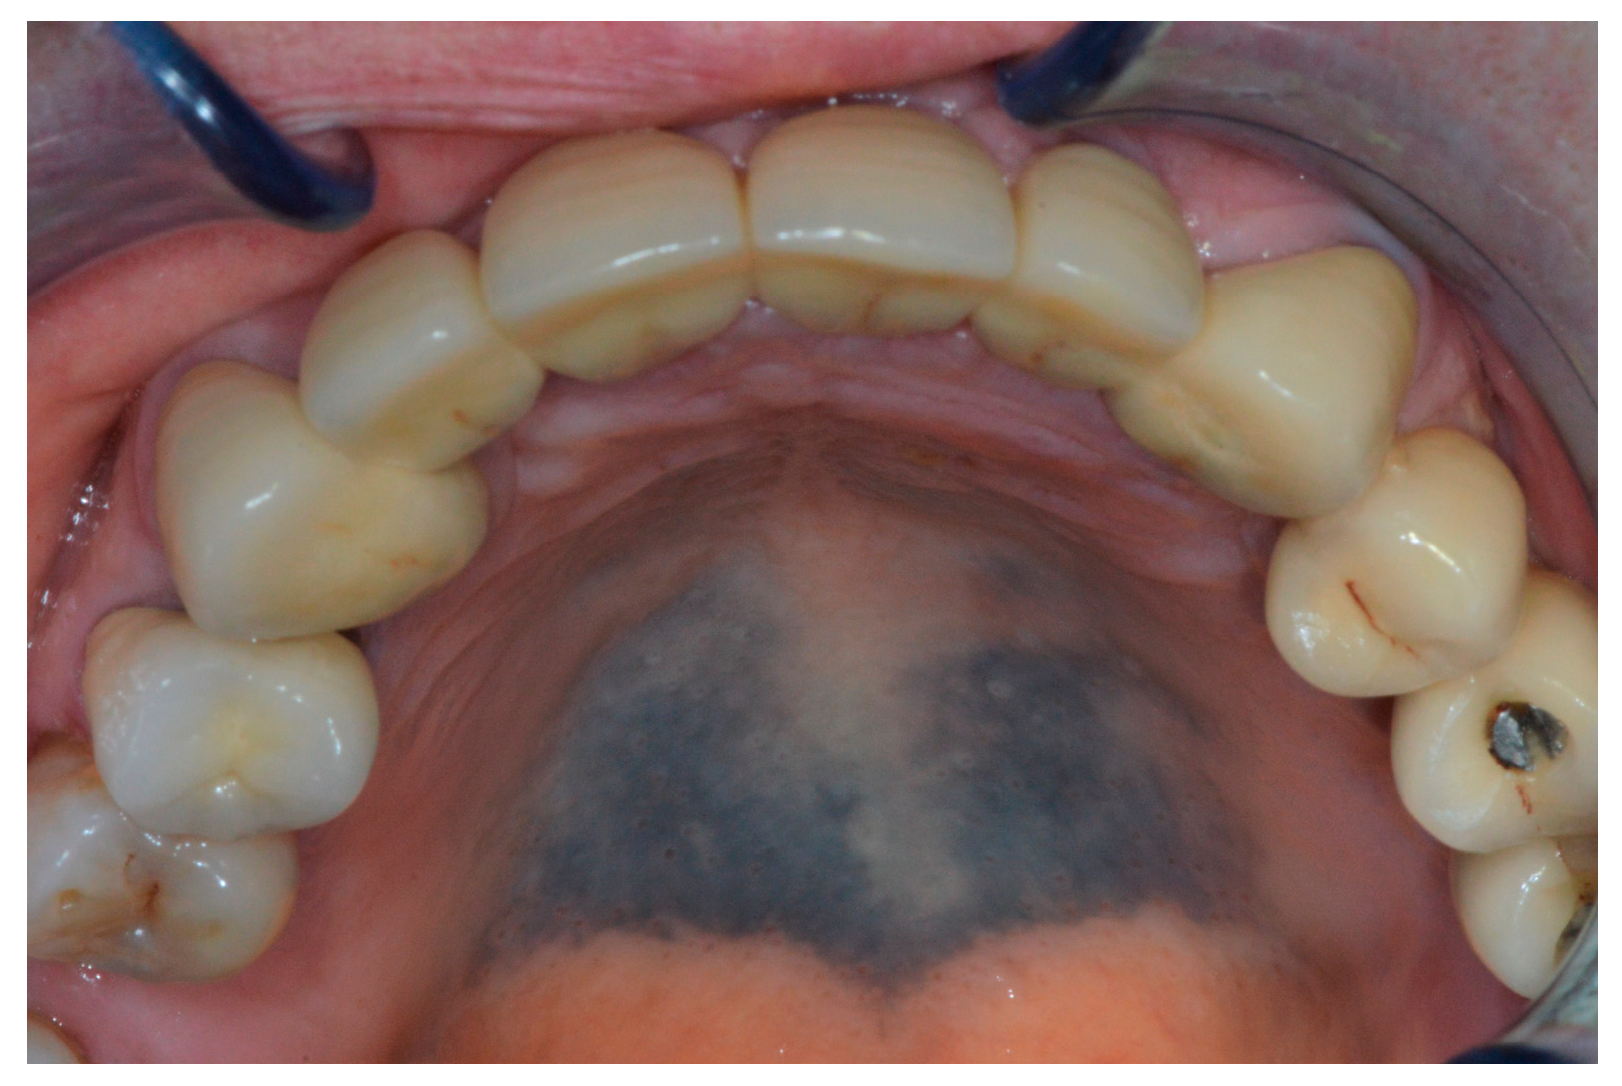

Hard Palate Hyperpigmentation Induced by Chloroquine: A Case Report †

2. Case Report